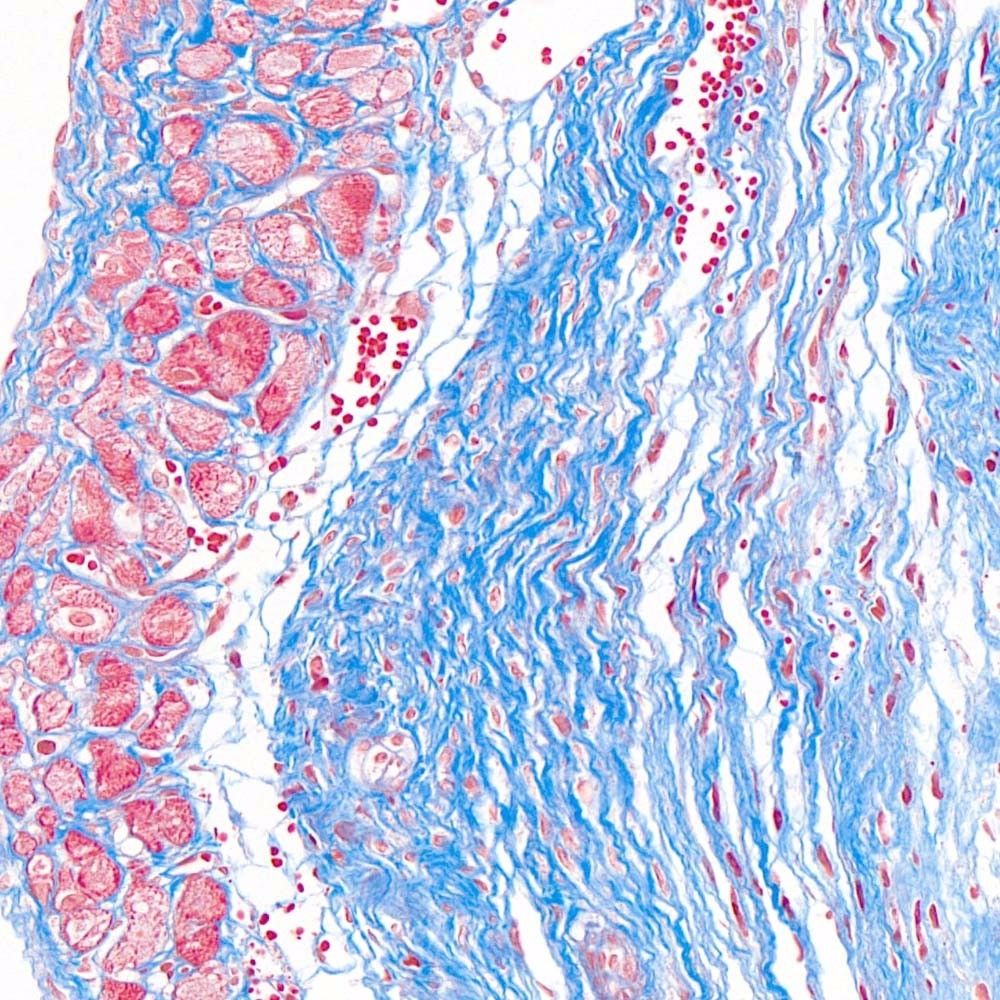

MASSON(馬松)染色實驗過程中常見問題和解決方法由普拉特澤生物技術為大家總結分享。本文是關于MASSON染色實驗的最后一篇介紹,前面我們深入了解了MASSON染色:原理、步驟與實例、如何進行MASSON染色?、MASSON染色方法及其在實驗室的應用可以點擊標題直接傳送回去學習的哦。普拉特澤生物病理檢測平臺承接MASSON實驗外包上百例,早就為大家把實驗過程中要踩的雷、吃的虧幫大家吃完了,現在我們就來看看,實驗過程中還有哪些常見的問題和解決方法吧!

除了以上常見問題外,實驗者在操作過程中還應注意以下幾點:首先,蘇木素用于細胞核的染色,染色時間可根據實際情況自行調整;其次,MASSON復合染色液經磷鉬酸分化時須用顯微鏡控制,確保肌纖維和膠原纖維呈現正確的顏色;最后,組織固定是實驗成功的關鍵,應選擇合適的固定劑并控制固定時間。